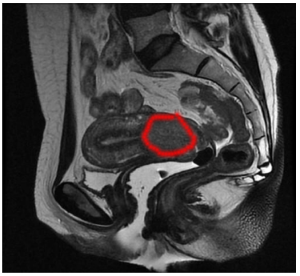

Paciente de 45 anos queixa-se de sangramento genital quase que diariamente há 1 ano. Refere também dor pélvica com irradiação lombar. Sem vida sexual ativa no momento. Antecedentes obstétricos: 2G 2P normais. Tabagista 1 maço dia. Ao exame especular observava-se o colo com orifício externo irregular e sem lesão macroscópica aparente na exocérvice. Ao toque retal os paramétrios estão livres. Exame de citologia cervico-vaginal com resultado compatível com lesão intra-epitelial de alto grau e biópsia do colo com diagnóstico de adenocarcinoma in situ. A figura representa o exame de ressonância magnética de pelve.

Em resumo, temos uma paciente com sangramento genital e dor lombar, sintomas que devem chamar nossa atenção. Na nossa investigação, foi encontrada um achado de adenocarcinoma in situ, mas com exame físico do colo aparentemente normal. Mas se avaliamos a nossa ressonância, vemos uma lesão de dimensões razoáveis no colo uterino e se estendendo até para o corpo uterino, percebem? Veja na imagem a abaixo a lesão circundada em vermelho:

Portanto, temos uma dissociação entre o anatomopatológico, de uma neoplasia não invasiva, da imagem, que mostra uma lesão aumentada de tamanho e acometendo todo o colo do útero, e por que não também da clínica com dor lombar associada (possível sinal de doença mais avançada)?

Dessa forma, é imprescindível obtermos uma amostra tecidual que seja compatível com a nossa suspeita clínica, o que não temos até agora – e a principal opção para tal é a conização, que permite a retirada de uma amostra tecidual maior. Mesmo que não tivéssemos a ressonância, a conização para amostra tecidual completa seria essencial na condução desse caso.

Se estivéssemos diante de um adenocarcinoma in situ, o tratamento recomendado seria cirúrgico com histerectomia. No entanto, pela imagem, parece um tumor de tamanho maior que 4 cm, com invasão de paredes vaginais e paramétrios excluídos pelo exame físico.

Até que se prove o contrário, um tumor no estadio IB3, candidato à quimiorradioterapia. Veja como a interpretação dos exames e o raciocínio diagnóstico muda completamente o tratamento e prognóstico dessa paciente.